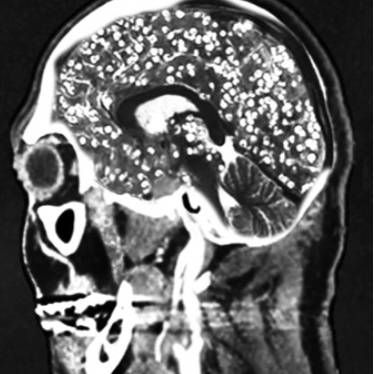

!['돼지고기 촌충'이라 불리는 갈고리촌충의 유충은 혈액을 타고 뇌에 침범해 두통과 발작을 일으키기도 한다. /사진= 유튜브 Chubbyemu]](https://img3.daumcdn.net/thumb/R658x0.q70/?fname=https://t1.daumcdn.net/news/202503/29/moneytoday/20250329132948792hmwg.jpg)

'기생충이 몸 안에 들어오면 음식물을 대신 먹어 살이 빠질 것'이란 속설이 있습니다. 지난해 체중 감량에 어려움을 겪던 미국의 20대 여성이 기생충 알이 든 캡슐을 먹고 다이어트하려다 뇌·목·얼굴·혀·간·척추 등에 기생충이 퍼져 끔찍한 부작용에 시달렸다는 사연이 전해졌습니다. 또 2011년 중국의 한 여대생은 취업난에 시달리던 중 다이어트를 위해 회충알을 다량 섭취해 병원에 실려 갔는데요. 그는 '부화하지 않은 회충의 알을 먹으면 다이어트에 효과가 있다'는 말을 믿고 먹었다가 뱃속에서 회충이 한꺼번에 부화한 것으로 드러났습니다.